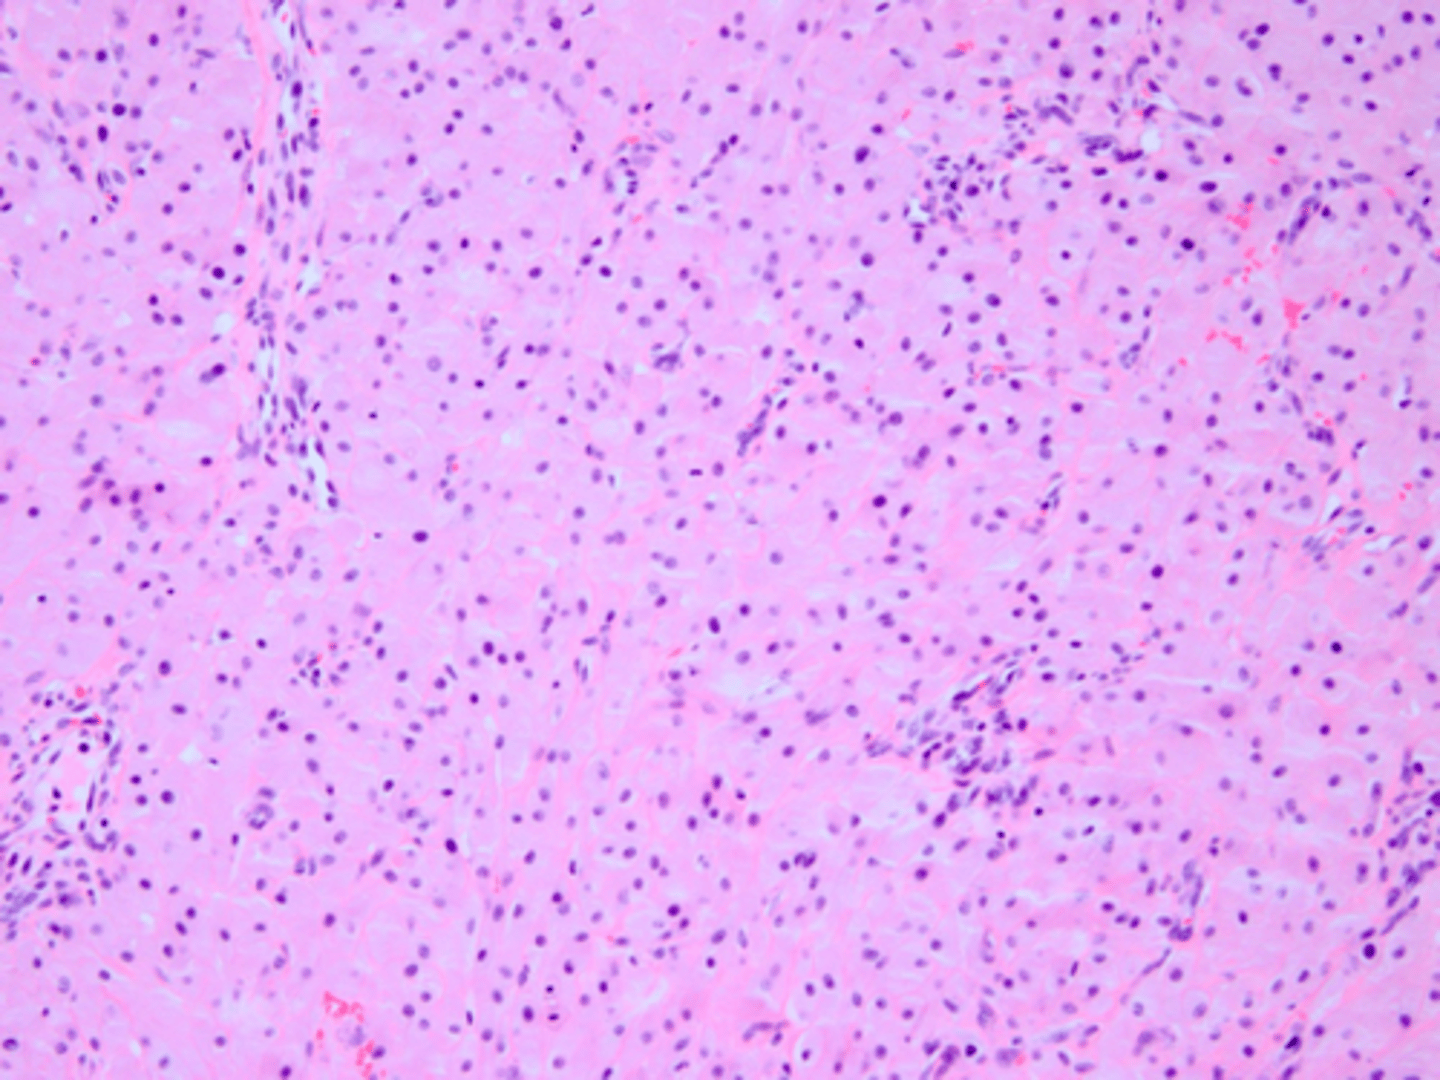

Neurofibroma

Neurofibroma

Patient presents with yellowish nodule on the dorsal tongue and gingiva. Histopathology shows interlacing bundles of spindle-cells with wavy nuclei. Patient also has several nodules all over the body that vary in size. What do you suspect the oral presentations to be?

Neurofibroma

interlacing bundles of spindle-cells with wavy nuclei is associated with what pathology?

local surgical excision

treatment for Neurofibroma: